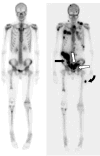

Fig. 3

A bone scan performed 15 months after diagnosis showed no evidence of extrapulmonary metastasis. A subsequent bone scan, taken 2-1/2 years post diagnosis, demonstrates new 99mTc-MDP uptake in multifocal bone metastases and omental metastasis (black arrow), as well as serosal calcification involving the sigmoid colon (white arrows) and soft tissue calcification in the left thigh (curved black arrow).